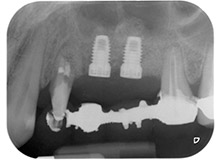

postoperative Röntgenaufnahme

Abb. 16: Die postoperative Röntgenaufnahme zeigt die eingesetzten Implantate mit apikal erkennbarem Knochenersatzmaterial vom internen Sinuslift. Auch um die Wurzel des Zahns 24 ist Knochenersatzmaterial von der GTR sichtbar.